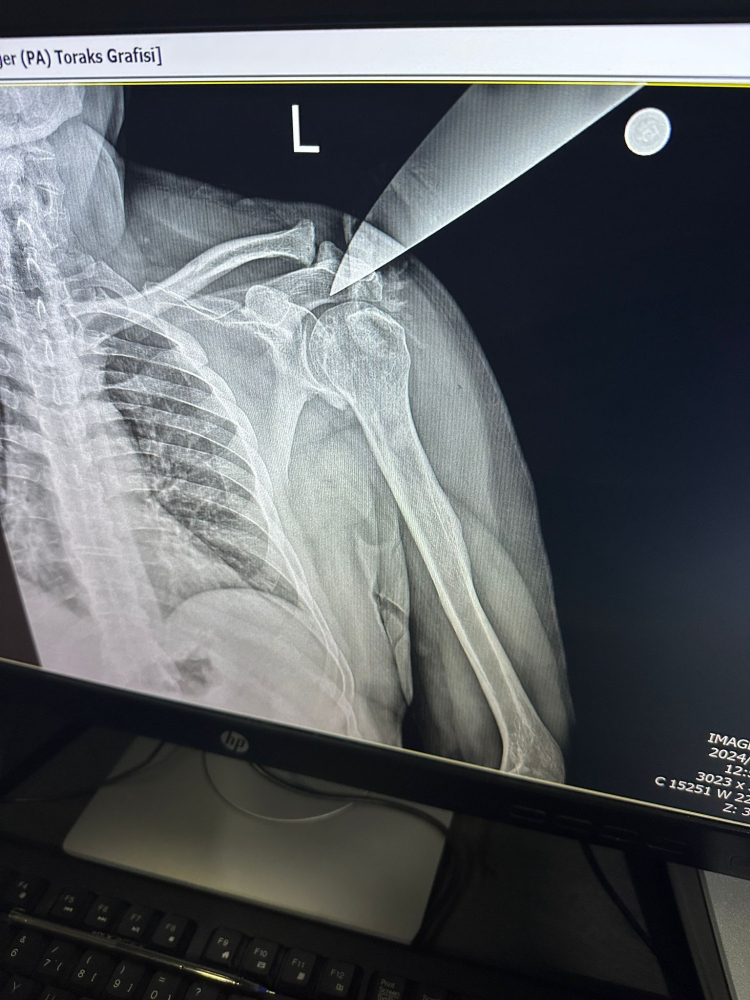

İhbar üzerine olay yerine gelen sağlık ekipleri, yaralı doktoru Yüksek İhtisas Eğitim ve Araştırma Hastanesine sevk ederken, doktorun omzuna saplanan bıçak ameliyatla alındı.